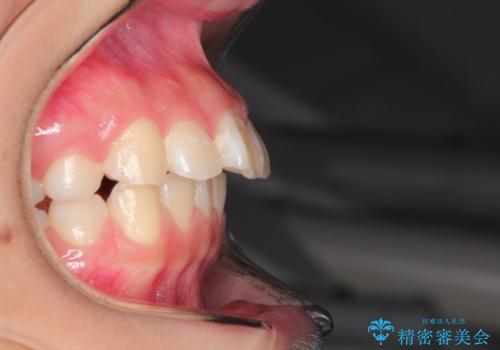

- 前歯が出ているのを主訴に来院されました。

上の前歯が前方に傾斜しており、上の前歯と下の前歯が接触していない状態でした。

上の奥歯を後方に移動させて、前歯を引っ込める計画としました。